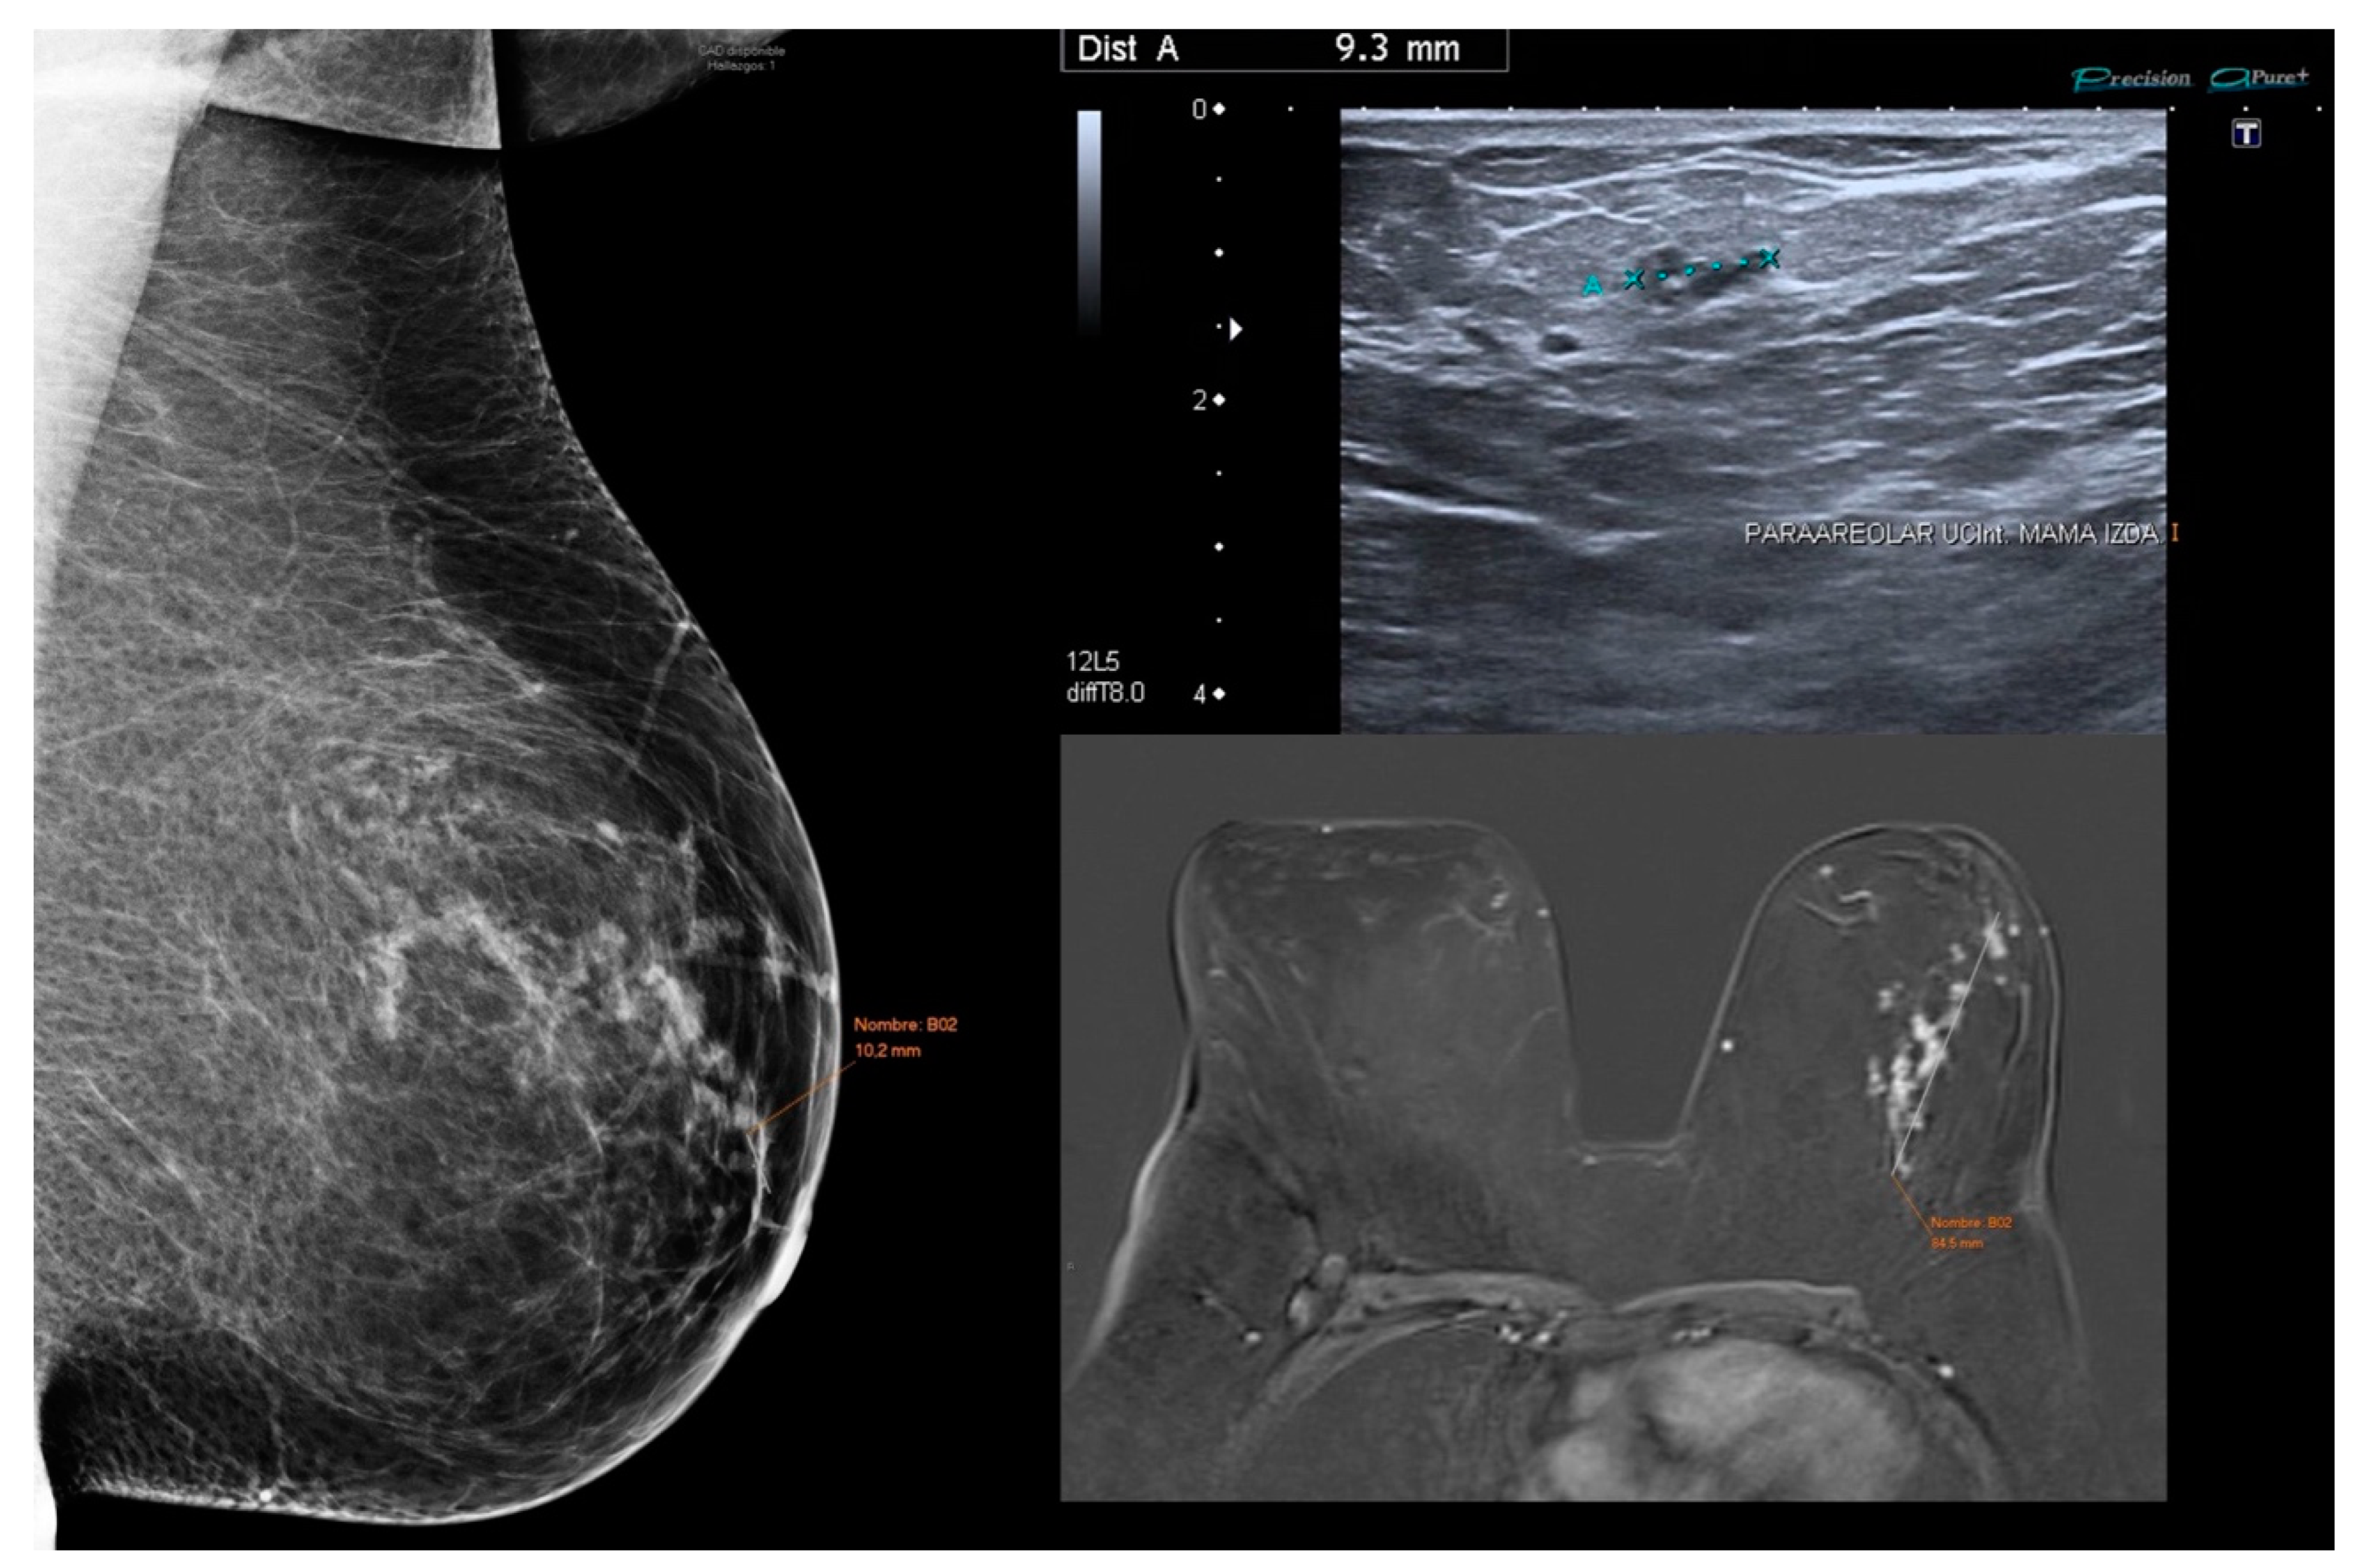

3.2. Mammographic Features

3.3. US Features

3.4. MRI Features